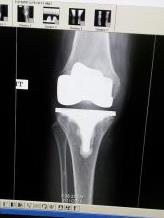

After Surgery: